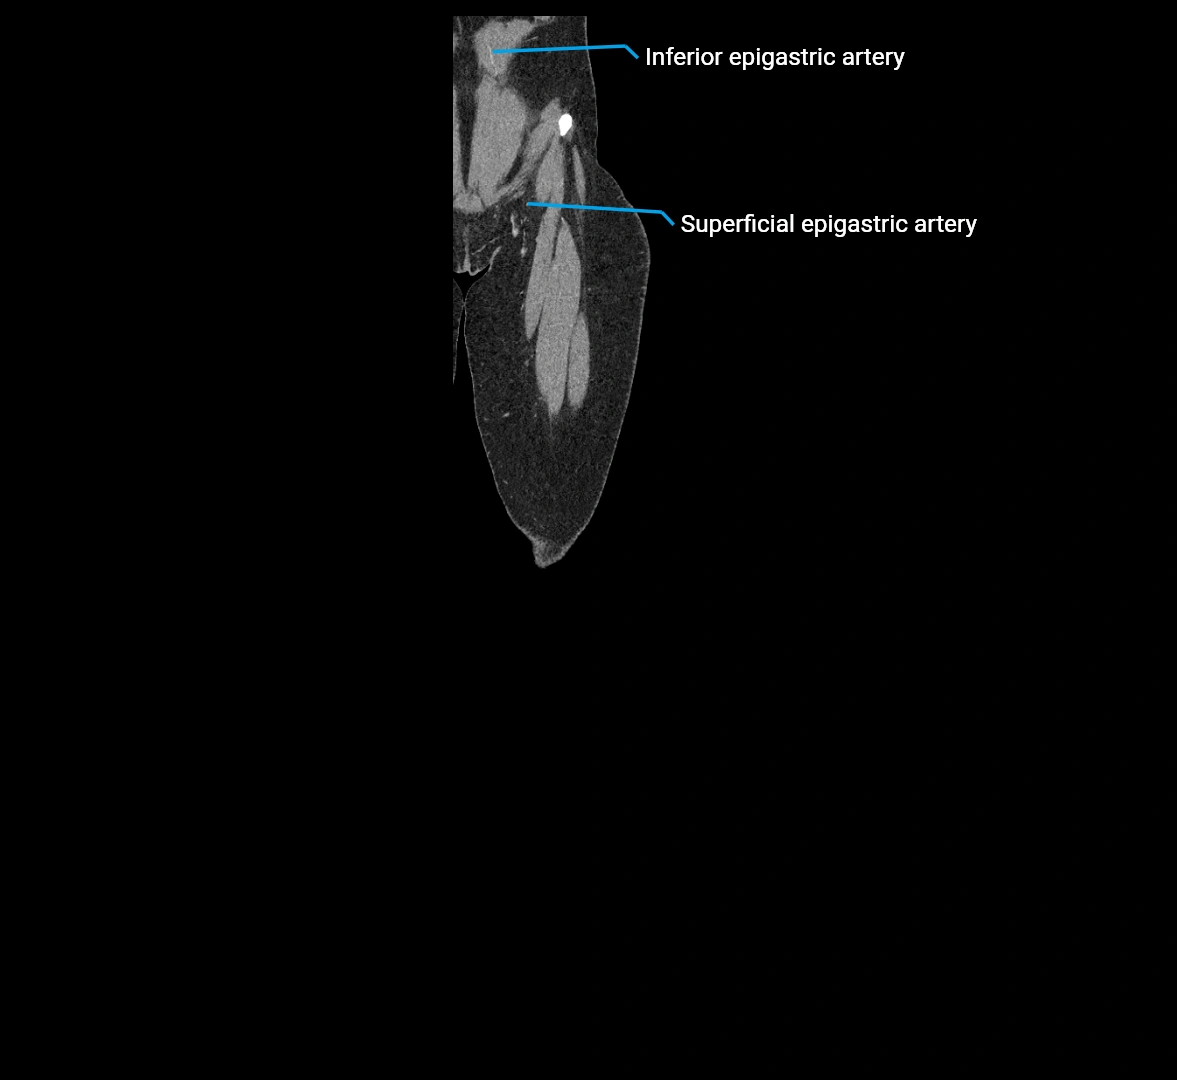

CT images

image

Contrast-enhanced CT (CTA):

• Gold standard for abdominal aortic imaging

• Provides excellent detail of lumen, wall, aneurysm, thrombus, and branch vessels

• Multiplanar and 3D reconstructions help in aneurysm measurement, stent graft planning, and dissection evaluation